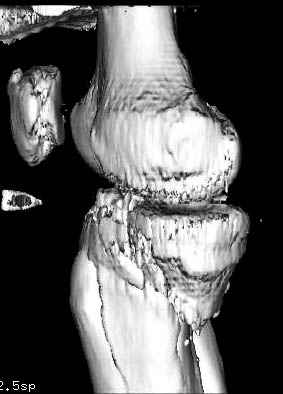

Здесь как раз тот случай, когда результат зависит не только от мастерства хирурга, но и от наличия современных методов исследования. Например, КТ которая поможет рассчитать направления шурупов и установку импланта. Кроме этого, поможет определиться с доступом.

На представленных предоперационных срезах КТ огромный задне-медиальный фрагмент расположен больше кзади, чем медиально. Для планирования, кроме поперечных срезов, надо ориентироваться на корональные срезы, которые укажут топографию верхушки медиального фрагмента.

Доступ к медиальной стороне задний или медиальный, через pes или в пространстве между medial gastroc мышцы.

Надеюсь, представленные снимки разных случаев помогут разобраться в тактике, и критика примется без личной обиды.